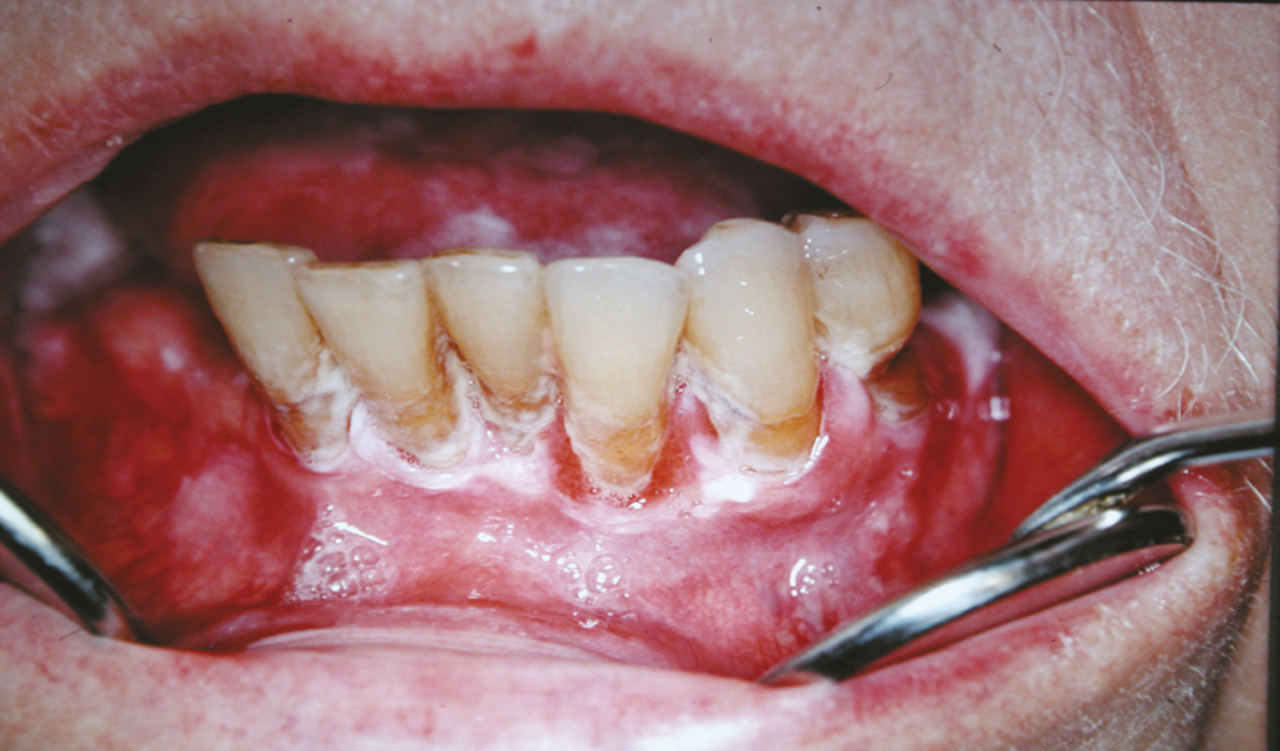

La leucoplasie homogène (fig. 1 ) a un aspect de plaque blanche clairement circonscrite, plane ou légèrement surélevée, lisse ou uniformément rugueuse, légèrement granulaire et ondulée, parfois traversée par de fines crevasses ou fissures sans érythème ou avec un érythème discret et uniforme sans érosions. Cette forme de leucoplasie, la plus fréquente, présente rarement des aspects histologiques inquiétants (dysplasies) et subit rarement une transformation maligne, au contraire des leucoplasies inhomogènes. Précisons que la dysplasie ne correspond à aucun aspect clinique. C’est un terme histologique désignant des modifications cytologiques et architecturales plus ou moins importantes.

La leucoplasie homogène (